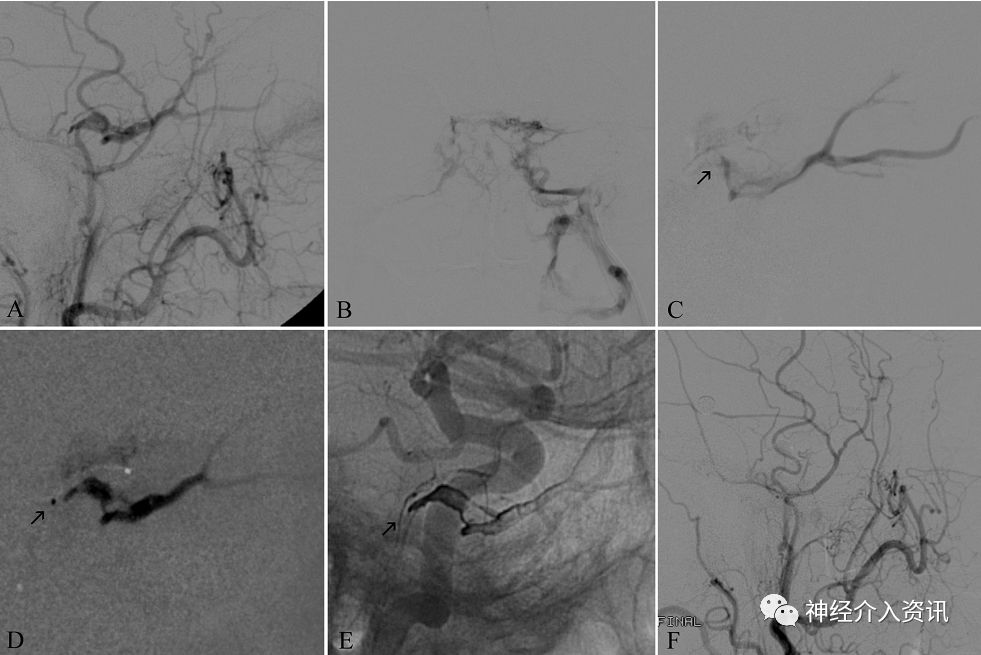

图3

(A) 左侧颈外动脉DSA,侧位,显示左侧硬脑膜颈动脉海绵窦瘘(DCCF),Barrow C型;

(B) 左侧颈静脉球DSA显示海绵窦和经左侧岩下窦到达左侧海绵窦;

(C) 左侧海绵窦后间隙超选DSA,侧位,通过Echelon(Medtronic)导管注射对比剂;

(D) 路图、侧位,显示Onyx注射剂到后间隙并逐渐充满前间隙闭塞DCCF;

(E) Onyx占据左侧海绵窦间隙最终铸型,栓塞前DCCF经这引流;

(F) 左侧颈外动脉DSA,侧位,显示DCCF完全闭塞。